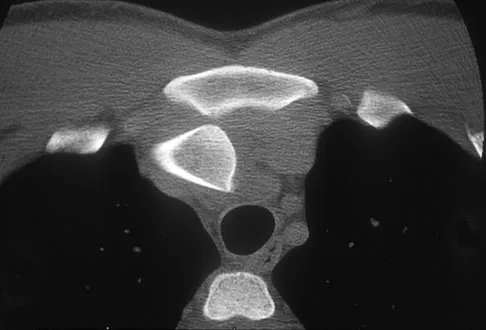

Figure 25 shows the CT scan of an adult patient who has neck pain following a motor vehicle accident. What is the most likely diagnosis?

Explanation